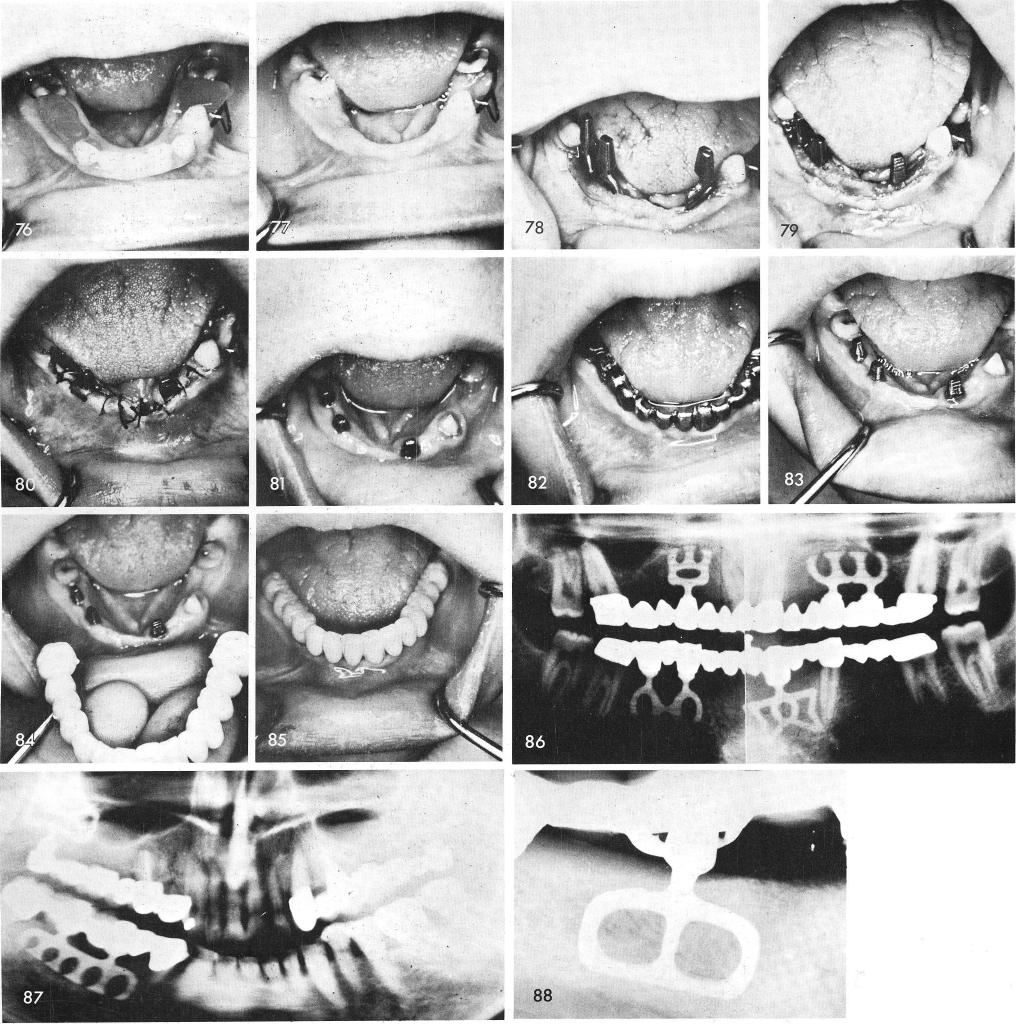

A case of partial anodontia with extremely knife-edged ridges, fig. 76, 77, needed the sup-port of two intra-tooth blades, fig. 78, that were carefully tapped into proper position by first widening the pyramidal shaped knife-edged ridge by removing several milimeters of bone at the crest, thus widening the occlusal table, fig. 79. The tissues were then sutured together, fig. 80. After tissue healing, fig. 81, impressions were taken for individual gold copings, fig. 82. One week later, the case was completed, figs. 83, 84, 85. The post-operative x-ray shows the entire case. It also reveals that the twelve year molars did not have to be involved for added support, fig. 86.

Fig. 87 through 102 shows other cases using intra-tooth bladevents.

1 Tapping of two intratooth mandibular blade implants in knife-edged ridge